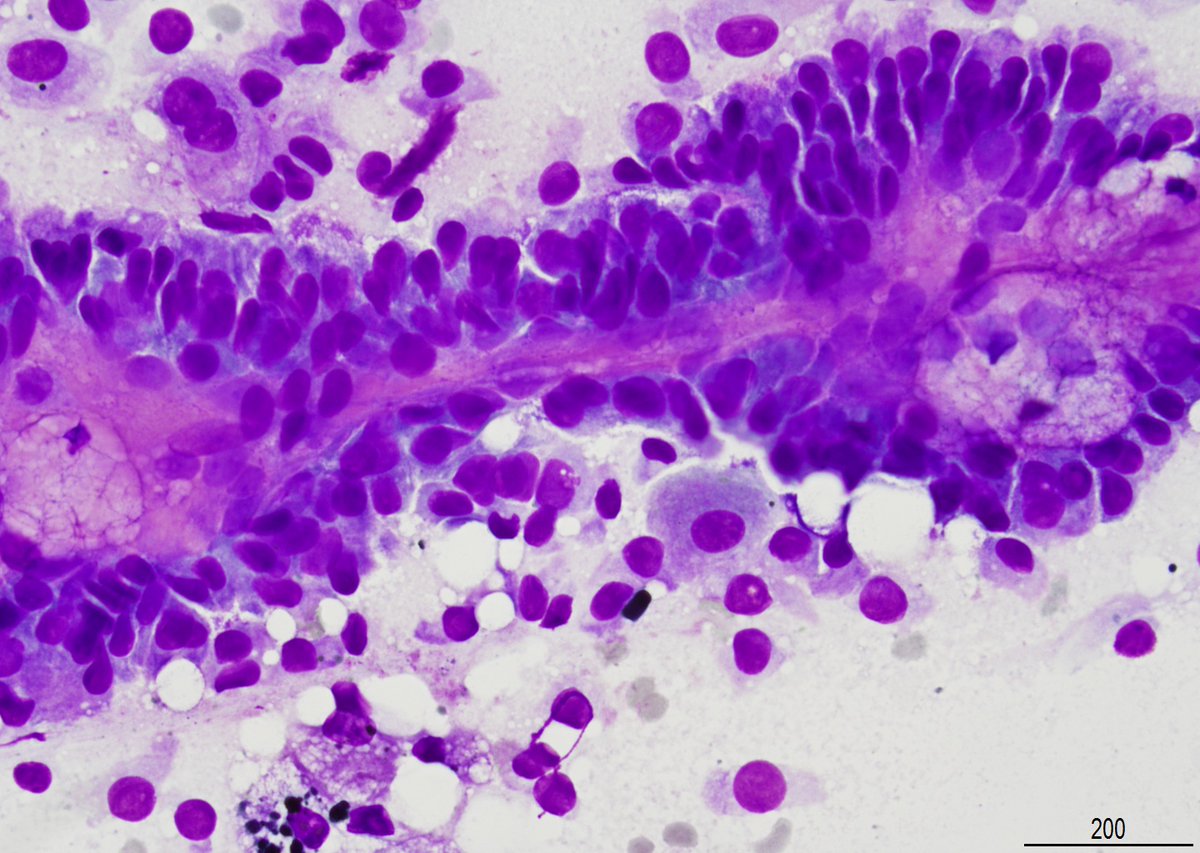

"BOW TIE". Papillary thyroid carcinoma. #FNA Thyroid. #Entpath #endopath #pathology #pathtwitter #PathTweetAward @MSWPathology @MyCytopathology @SamKhader